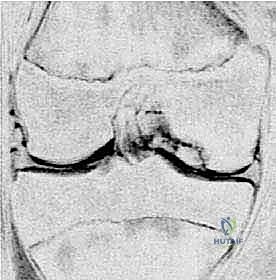

2. التصوير بالأشعة السينية (X-rays)

هي الخطوة التصويرية الأولى والأساسية. يطلب الدكتور هطيف صوراً بوضعيات محددة (أمامية خلفية، جانبية، وضعية النفق Notch view، ووضعية شروق الشمس Skyline view) أثناء الوقوف (تحميل الوزن). تساعد الأشعة السينية في رؤية العيوب العظمية، وتحديد حجم الآفة، واكتشاف أي أجسام حرة (Loose bodies) متكلسة داخل المفصل.